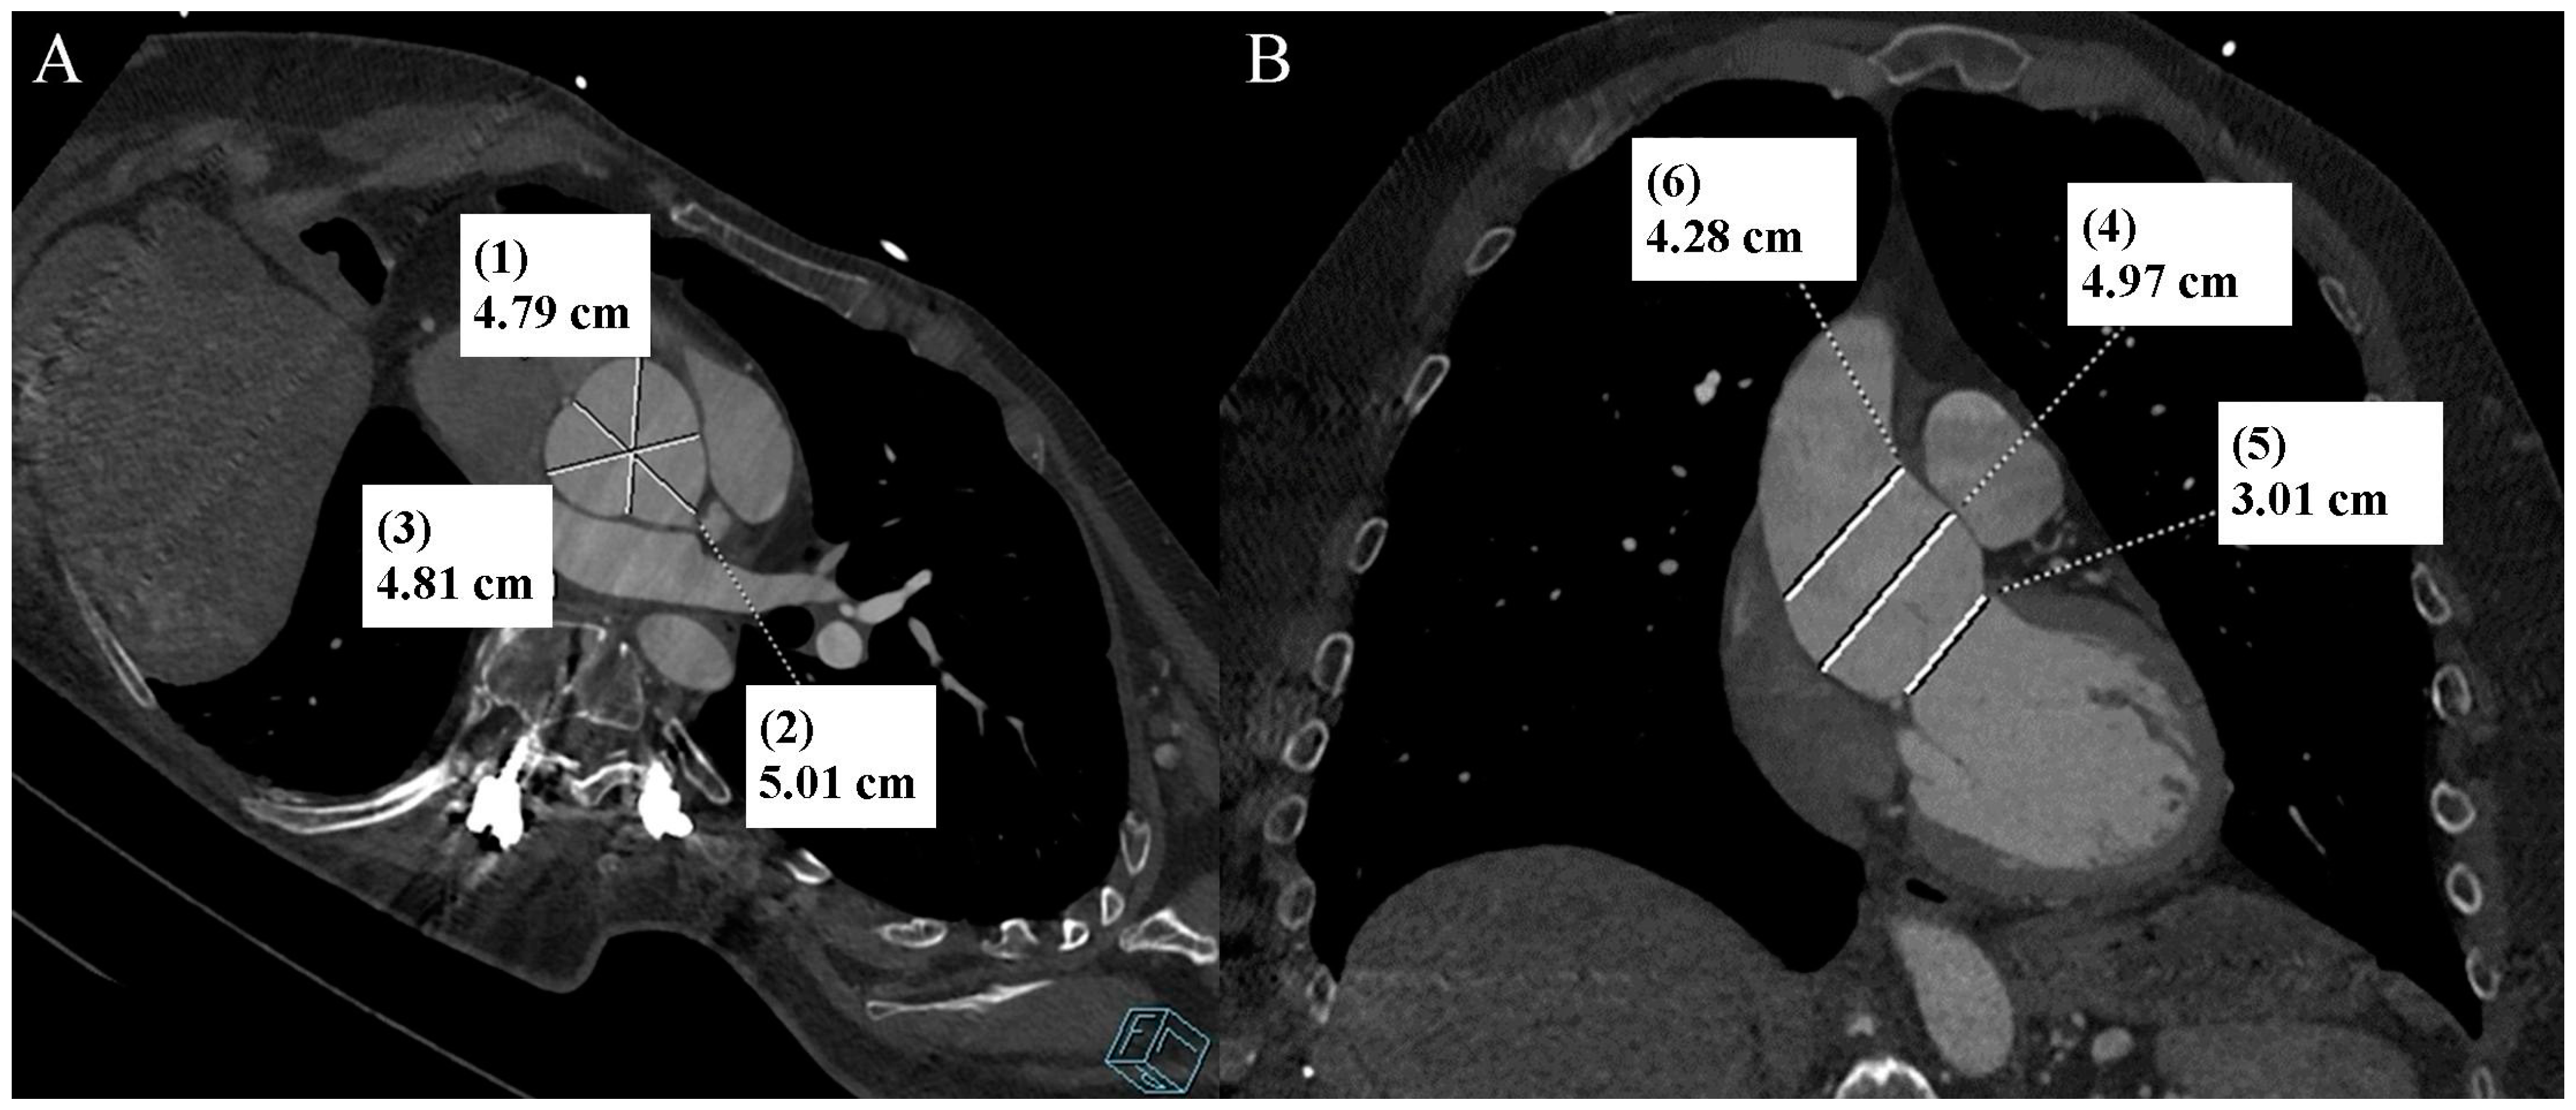

Figure 1.

Thoracic aorta computed tomography angiography. Aortic bulb aneurysm. (A). Multiplanar reconstruction. View parallel to the aortic annulus plane. Subsequent measurements were made between the commissures of the aortic valve leaflets and the midpoints of the aortic valve leaflets. (B). Multiplanar reconstruction. Perpendicular view to the aortic annulus plane in the long axis. The designations (1–6) indicate subsequent measurements: aortic annulus—3.01 cm (5); aortic bulb—4.79 cm (1), 5.01 cm (2), 4.81 cm (3), 4.97 cm (4); sinotubular junction—4.28 cm (6).